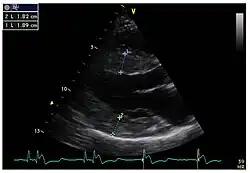

Die linksventrikulären strukturellen Veränderungen des Herzens finden sich bei Morbus-Fabry-Patienten häufig. Mittels Echokardiografie (Ultraschalluntersuchung des Herzens) oder kardialer Magnetresonanztomographie (MRT) können die meist konzentrischen Hypertrophien[80][81] sichtbar gemacht werden. Da mit zunehmendem Alter durch die Ersatzfibrose die linksventrikuläre Hinterwand des Herzens immer dünner wird, ist die Messung der Septumdicke – das ist die Stärke der Scheidewand zwischen linker und rechter Herzhälfte – besonders wichtig. Unabhängig von den strukturellen Veränderungen scheint die Systole, die Phase, in der das Blut aus der linken und rechten Herzkammer herausgepresst wird, bei der Messung mit konventionellen Methoden weitgehend erhalten zu bleiben.[80][81][82][91] Die durch Morbus Fabry verursachte Kardiomyopathie ist durch eine reduzierte Kontraktion und Relaxation des Herzmuskels gekennzeichnet. Gewebedoppler (sowohl tissue velocity imaging als auch strain rate imaging) kann die Herzmuskelfunktion quantifizieren.[7][92] Mit dieser Methode kann die Kardiomyopathie noch vor der Entwicklung einer linksventrikulären Hypertrophie diagnostiziert werden.[91][93]

- Echokardiografien von Patienten mit Morbus Fabry

-

Parasternale lange Achse: Deutlich sichtbar die linksventrikuläre Hypertrophie mit erhöhter Septumdicke. -

Parasternale kurze Achse: Die Aufnahme zeigt ebenfalls eine linksventrikuläre Hypertrophie. -

Gewebedoppler-Echokardiographie des Mitralanulus (Mitralring) mit nahezu normaler systolischer Funktion